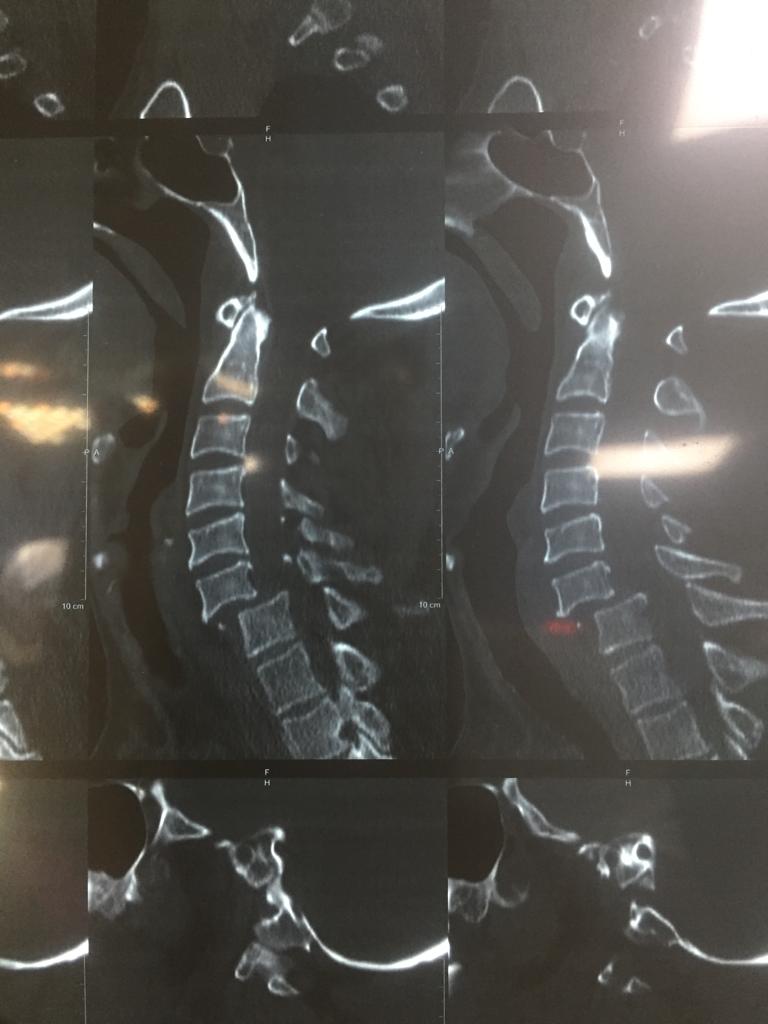

Cases